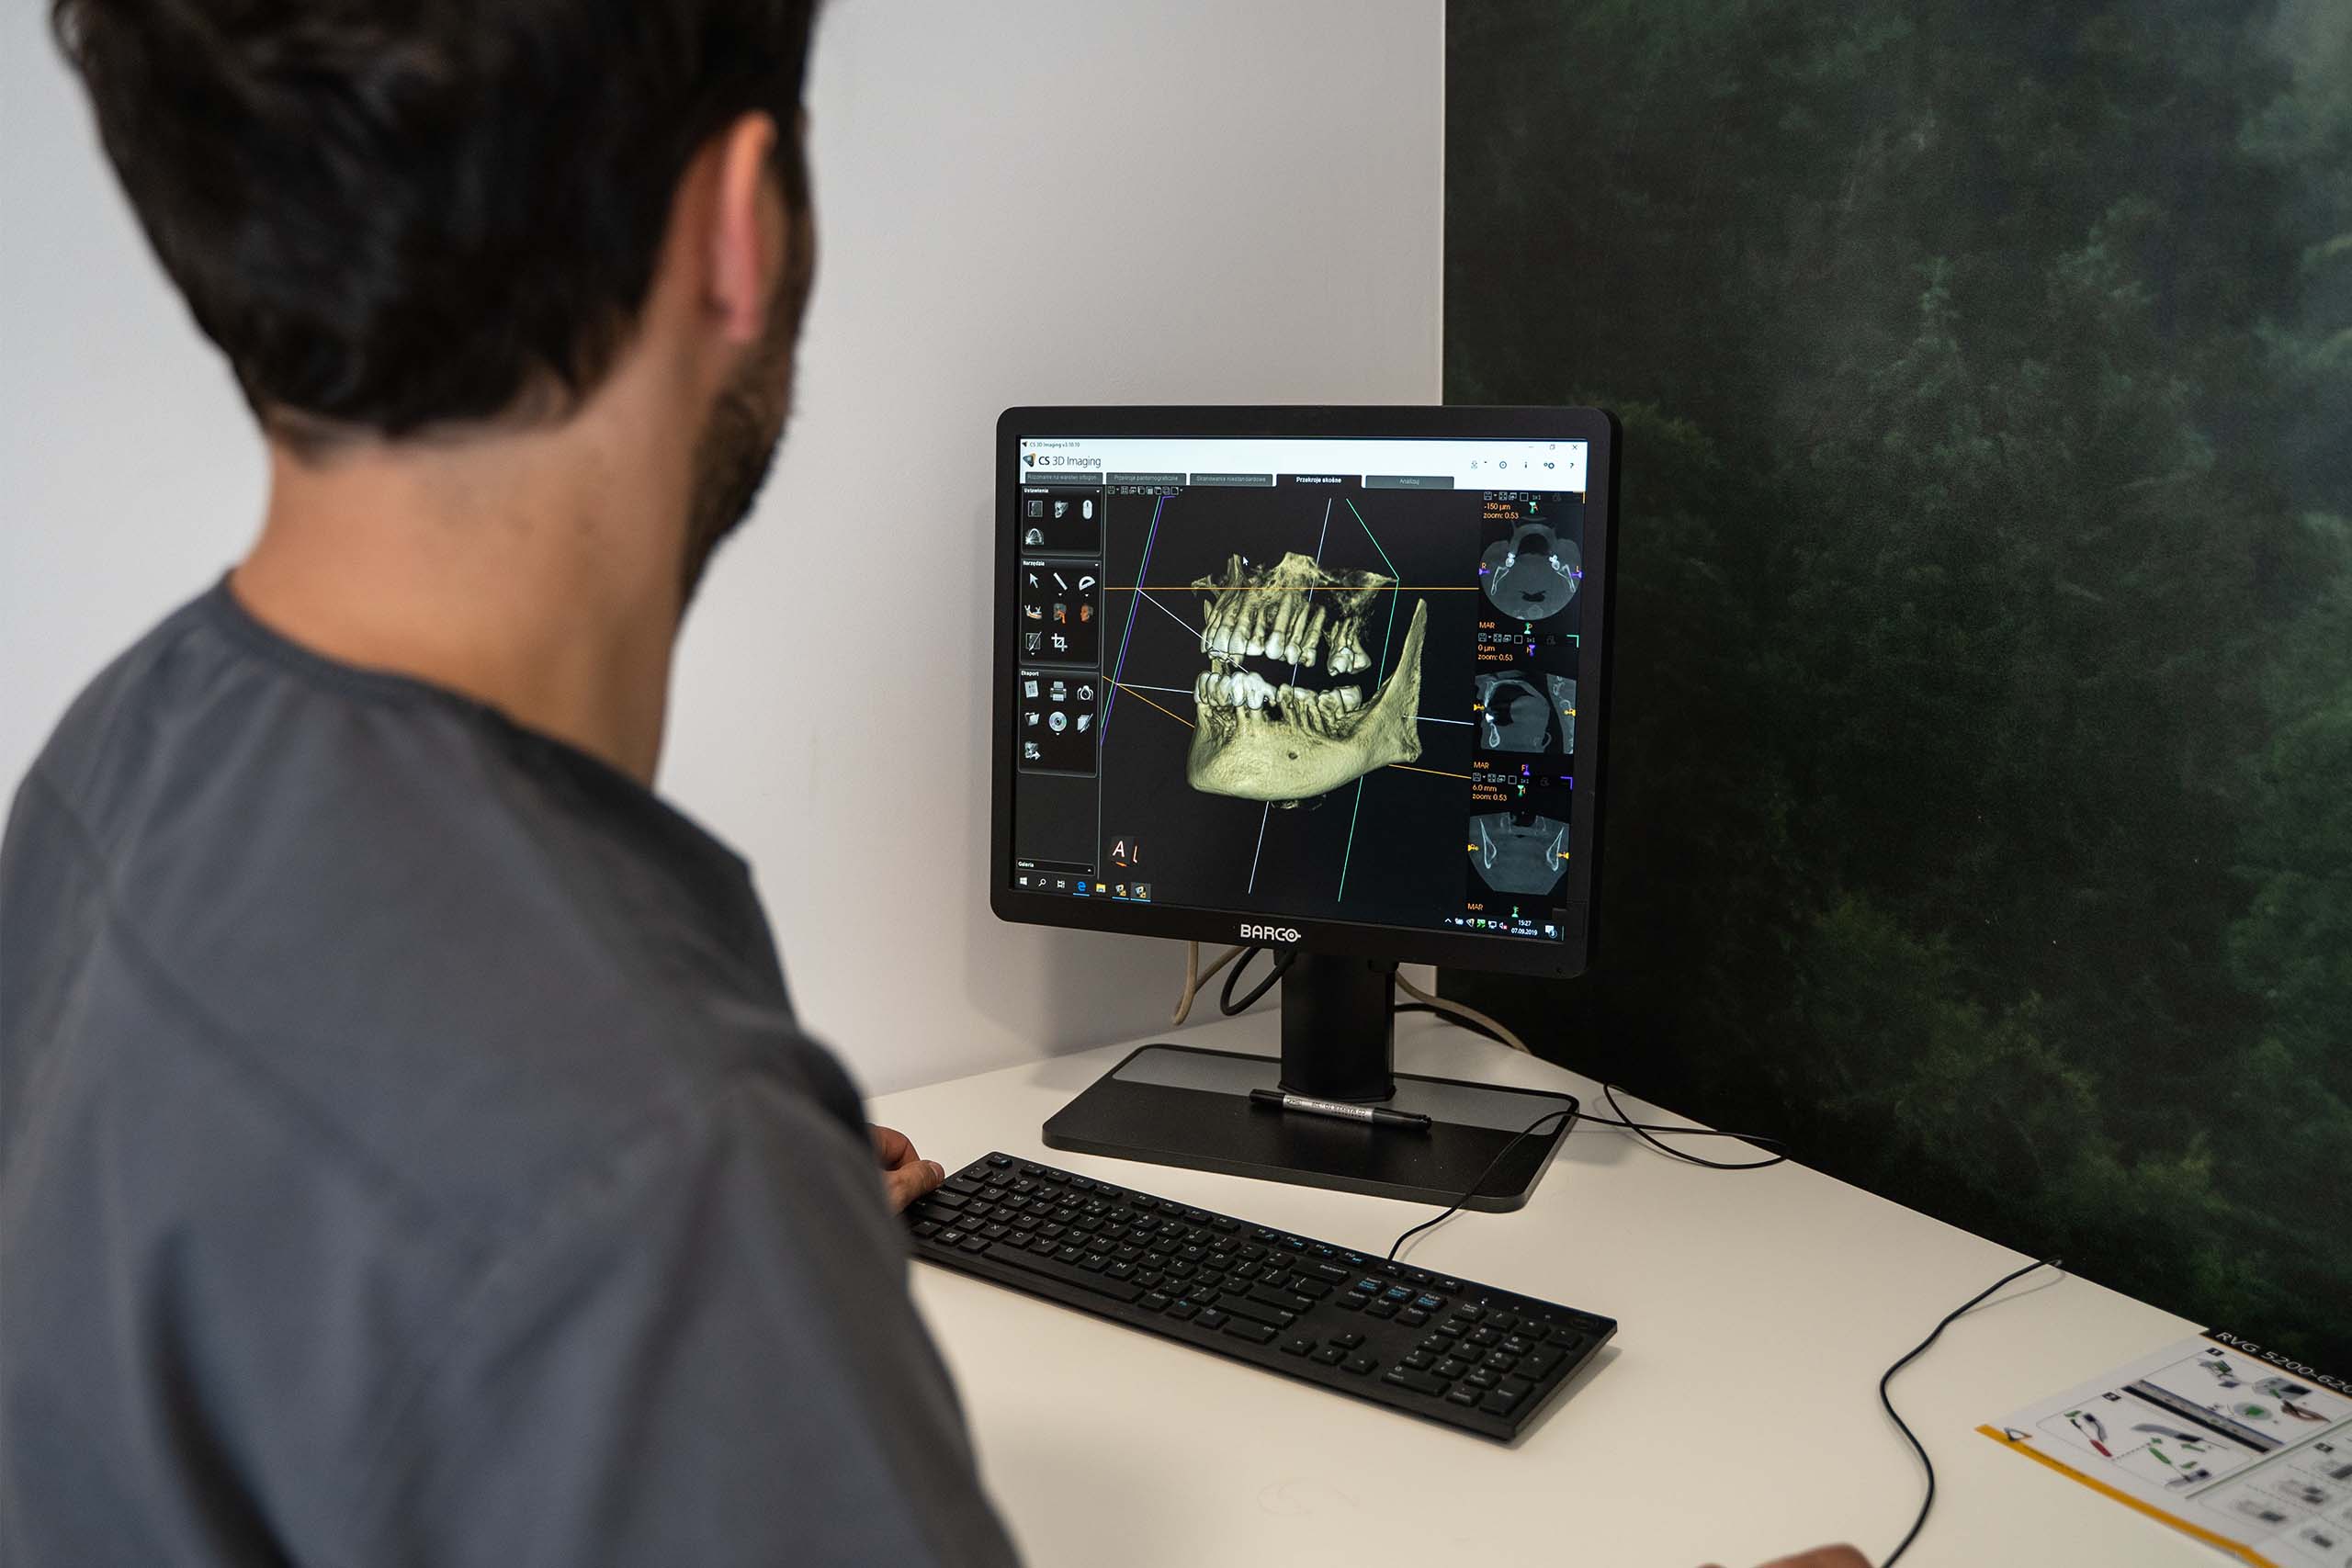

Dzięki zastosowaniu stożkowej wiązki promieniowania rentgenowskiego tomografia komputerowa pozwala na uzyskanie niezwykle precyzyjnych obrazów, odwzorowujących nawet najdrobniejsze szczegóły anatomicznej budowy głowy, przy jednoczesnym zminimalizowaniu dawki promieniowania oraz skróceniu czasu potrzebnego na badanie. Znacząco wpływa to na bezpieczeństwo i komfort Pacjentów, którzy nie muszą przygotowywać się wcześniej do procedury. Tomografia powinna być wykonywana zwłaszcza przed leczeniem ortodontycznym, chirurgicznym czy implantologicznym. To sprawdzona technika diagnostyczna stosowana przez lekarzy w renomowanych gabinetach.

Tomograf Kodak Carestream CS 9600 jest to system, który zapewnia najwyższą dostępną jakość uzyskiwanych obrazów oraz aż czternaście różnych pól obrazowania. Zastosowane w nim innowacyjne rozwiązania pozwoliły na osiągnięcie doskonałych efektów, przy jednoczesny zwiększeniu bezpieczeństwa użytkowania. Dzięki licznym funkcjom sprawdza się jako urządzenie diagnostyczne w wielu dziedzinach stomatologii. Tomografia wykonana przy jego użyciu jest przy tym wyjątkowo dokładna. Oznacza to, że podczas badania można bardzo precyzyjnie zobrazować wszystkie tkanki organizmu – to pozwala na szybkie postawienie jednoznacznej diagnozy oraz natychmiastowe wdrożenie odpowiednich metod leczenia.

Tomograf Kodak Carestream CS 9600 jest to system, który zapewnia najwyższą dostępną jakość uzyskiwanych obrazów oraz aż czternaście różnych pól obrazowania. Zastosowane w nim innowacyjne rozwiązania pozwoliły na osiągnięcie doskonałych efektów, przy jednoczesny zwiększeniu bezpieczeństwa użytkowania. Dzięki licznym funkcjom sprawdza się jako urządzenie diagnostyczne w wielu dziedzinach stomatologii. Tomografia wykonana przy jego użyciu jest przy tym wyjątkowo dokładna. Oznacza to, że podczas badania można bardzo precyzyjnie zobrazować wszystkie tkanki organizmu – to pozwala na szybkie postawienie jednoznacznej diagnozy oraz natychmiastowe wdrożenie odpowiednich metod leczenia.